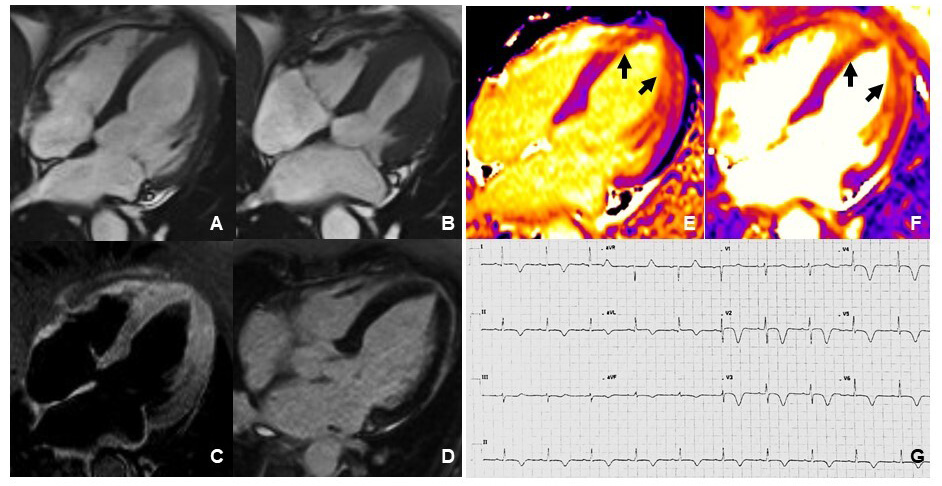

CMR is the gold standard non-invasive imaging tool in cardiovascular medicine for visualizing cardiovascular anatomy, quantifying chamber volumes and systolic function and characterize myocardial tissue [100]. Indeed it is able to identify and quantify non-vital areas, fibrosis and edema in the context of normal myocardium. Classic CMR appearance during the acute phase of TTS includes widespread myocardial edema, mostly distributed in the areas of contractile dysfunction [101], in the absence of significant replacement fibrosis at late gadolinium enhancement (LGE) imaging. However, presence of LGE areas has been reported [102], and linked to adverse outcomes [103]. Several bystander diseases associated with LGE areas might characterize patients with TTS, including previously unrelated myocarditis, AMI or known obstructive CAD [76, 104]. CMR should be performed in the acute phase, when available, in all TTS patients [22, 77] in order to differentiate TTS from other conditions with similar clinical presentation, such as myocardial infarction with non-obstructive coronary arteries (MINOCA) or myocarditis, and thus to guide the therapeutic decision-making process [105, 106, 107]. Additionally, performing early CMR would help identify typical complications of acute TTS, such as right ventricular involvement and ventricular thrombosis, which may be difficult to observe with TTE [108]. Unfortunately, CMR imaging cannot be always performed easily in the acute setting of TTS. The ESC position statement on TTS acknowledged this issue, suggesting to perform CMR preferentially for patients with dubious clinical presentation or suspected myocarditis [109]. CMR is also particularly useful in the subacute and chronic phase in order to evaluate residual edema and confirm the diagnosis, especially in case of less common presentations, such as in young, males or patients with atypical anatomical variants (midventricular [110], basal [111], and focal [112, 113] motion patterns) (Fig. 3, Ref. [72]). A low-grade myocardial edema may be still present at 3-month follow-up after the acute event, being linked to persistent symptoms as well as increased natriuretic peptide [114]. New advanced CMR techniques may provide an accurate and sensitive detection of edema and intramyocardial fibrosis and evaluation of myocardial chambers deformation (Feature-tracking CMR) similar to speckle-tracking echocardiography [115]. In particular, novel CMR mapping sequences allow a parametric quantification of interstitial expansion in the myocardium, with signal intensity mainly depending on extracellular water (T2 mapping) as well as fibrosis and infiltration (native T1 and extracellular volume mapping). Studies performed in the acute phase suggested concomitant increase of native T1 and T2 secondary to widespread edema [116, 117, 118]. High T2 values were related to lower acute LVEF [119] and delayed recovery along with native T1 [120]. At three months, persisting abnormalities can be detected [120, 121], while also in the long-term (more than one year after the acute event) native T1 has been described as persistently elevated [65] suggesting long lasting effect of the TTS event. However, native T1 is a very sensible imaging biomarker, influenced by a variety of factors including edema and, among others, previous chemotherapy [122], chronic kidney disease [123], arterial hyertension [124]. Hence, the presence of higher than normal native T1 values even before the TTS attack cannot be excluded in such a comorbid population. Fig. 4 shows CMR imaging findings of a TTS patient two weeks after the acute event.

Fig. 4.Cardiovascular Magnetic Resonance imaging and ECG of a TTS patient performed 2 weeks after the acute event. Frames taken from cine sequences (balanced steady-state free-precession) showing normal kinesis of the left ventricle, end-diastole (A) and end-systole (B). T2-STIR imaging shows increased signal intensity consistent with myocardial edema at mid-apical left ventricular site (C). Late gadolinium enhancement imaging revealed absence of replacement fibrosis (D). Native T1 mapping imaging showed increased signal intensity at mid-apical left ventricular site (arrows in E) paralleling increased signal detected by T2 mapping imaging (arrows in F). ECG showed diffuse T-wave inversion (G).